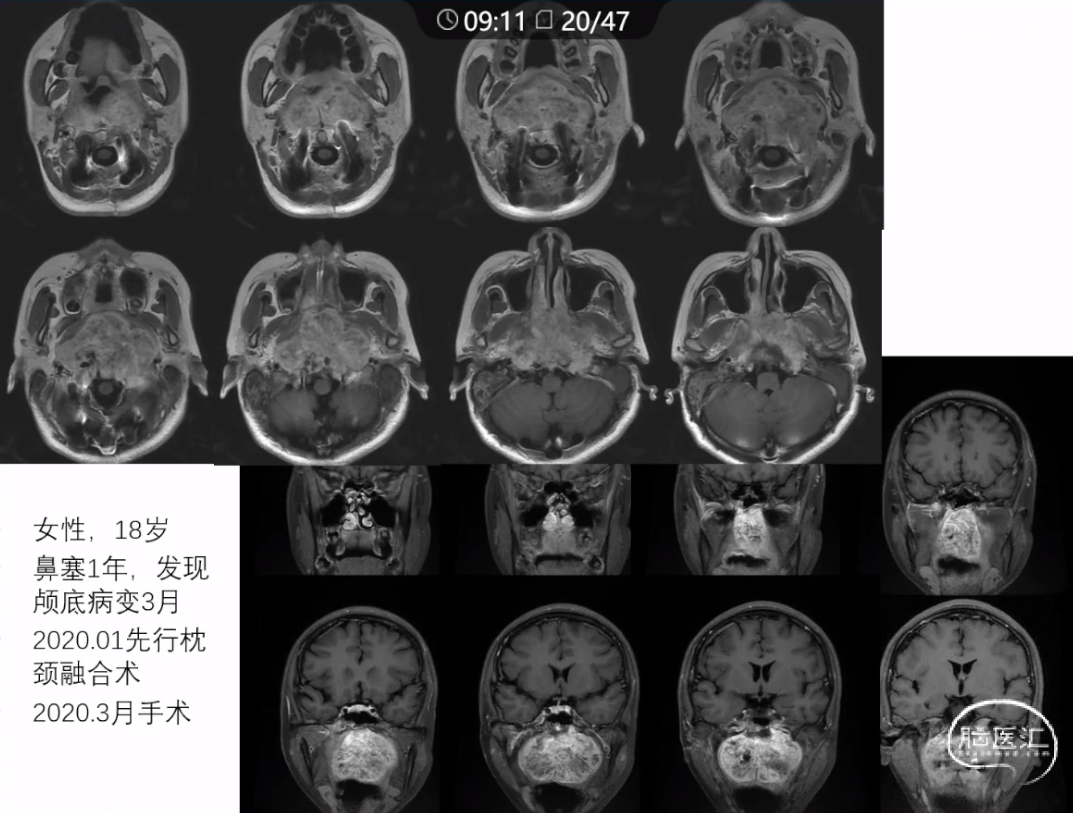

本文主要内容为:脊索瘤临床特点、治疗选择,以及多个手术病例。